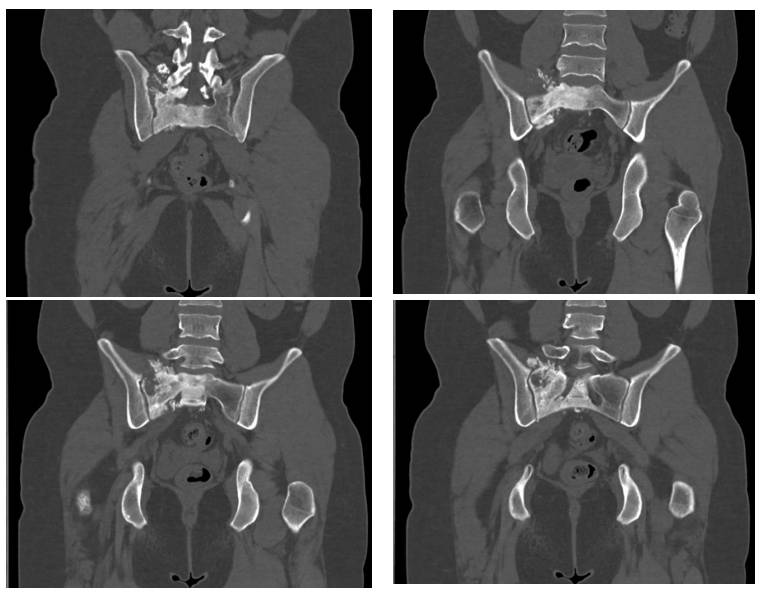

Ameliyat Öncesi: Tomografide sağ sakroiliak bölgede düzensizlik ve sklerozun eşlik ettiği tümör dokusu görülmekte